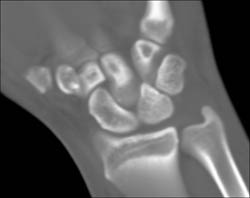

Diagnosis

Cellulitis